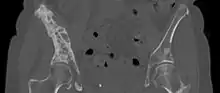

| 3D rendered CT scan of bone metastases of the hip bone, in a 60 year old woman with parotid gland cancer. Large lesions are seen on the ilium on the more distant side. Involvement of the vertebral column has caused a compression fracture. | |